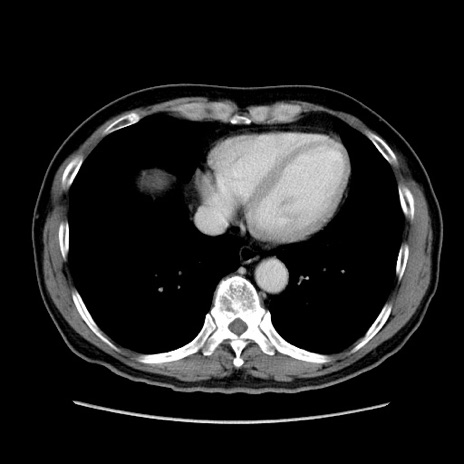

症例34(横断像)

【症例】60歳代 男性

【主訴】右鼠径部膨隆

【現病歴】1年程前より右鼠径部膨隆あり。自己にて還納可能だったため放置していた。3時間前より右鼠径部の脱出を認め、還納困難となり受診。

【既往歴】高血圧

【身体所見】右鼠径部に小児頭大の膨隆あり。弾性硬であり、用手還納は困難。左鼠径部にも膨隆を認める。脱出はなし。

【データ】WBC 15500、CRP 測定なし